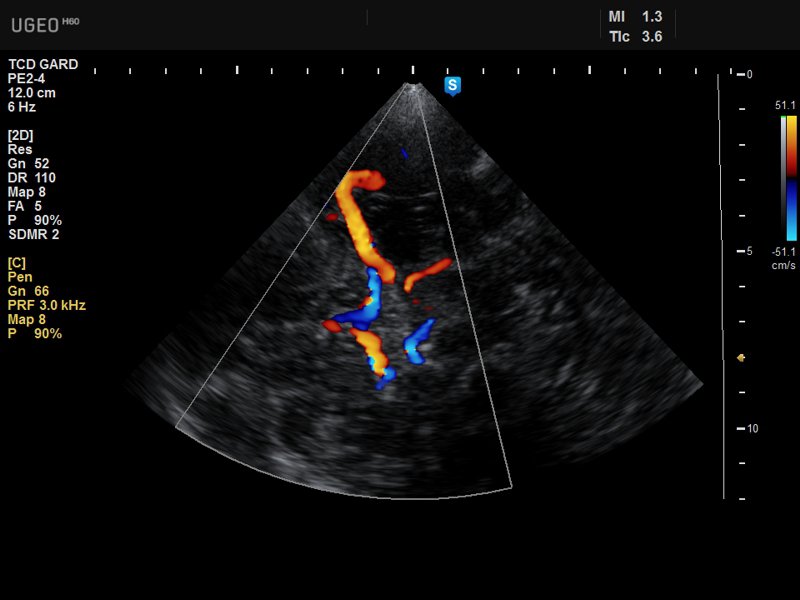

Siêu âm doppler xuyên sọ cũng là thủ thuật được thực hiện tương tự siêu âm doppler thông thường. Thủ thuật siêu âm xuyên sọ đưa sóng siêu âm thăm dò vào những vị trí có xương sọ mỏng hơn các nơi khác. Sóng sẽ thu về các thông tin liên quan tới hình ảnh của toàn sọ, đặc biệt là các buồng chứa chất lỏng, dịch tủy trong não.

Siêu âm theo 3 vị trí chủ chốt:

- Siêu âm qua cửa sổ thái dương: Độ dày của xương thái dương có sự khác biệt giữa các sắc tộc hoặc giới tính nên bác sĩ sẽ cân nhắc tới yếu tố này trước khi chỉ định thực hiện siêu âm tại vị trí này. Khi thực hiện, bác sĩ sẽ đặt đầu dò phía trên gò má khu vực đằng trước tai, thực hiện kiểm tra và lựa chọn vị trí thăm dò tốt. Máy tính sẽ ghi nhận tín hiệu của động mạch não trước, giữa và sau ngay khi sóng siêu âm đạt tới độ sâu phù hợp;

- Siêu âm qua cửa sổ ổ mắt: Trước khi thực hiện bác sĩ sẽ hướng dẫn kỹ thuật cho bệnh nhân vì kỹ thuật siêu âm vùng ổ mắt đòi hỏi nhãn cầu của bệnh nhân phải đứng yên. Khi thực hiện, bệnh nhân tập trung hướng tầm nhìn của bản thân về phía trước, bác sĩ sẽ đặt đầu dò ở mí mắt, sử dụng một lực nhẹ vừa đủ để gel siêu âm tiếp xúc với mặt da và ghi nhận kết quả siêu âm;

- Siêu âm qua cửa sổ dưới chẩm: Xương chẩm là xương nằm dưới cùng bên phải hộp sọ, phủ lên thùy chẩm. Khi thực hiện siêu âm, bệnh nhân cần phối hợp với bác sĩ để tìm điểm đặt đầu dò, sau đó siêu âm và ghi nhận kết quả.